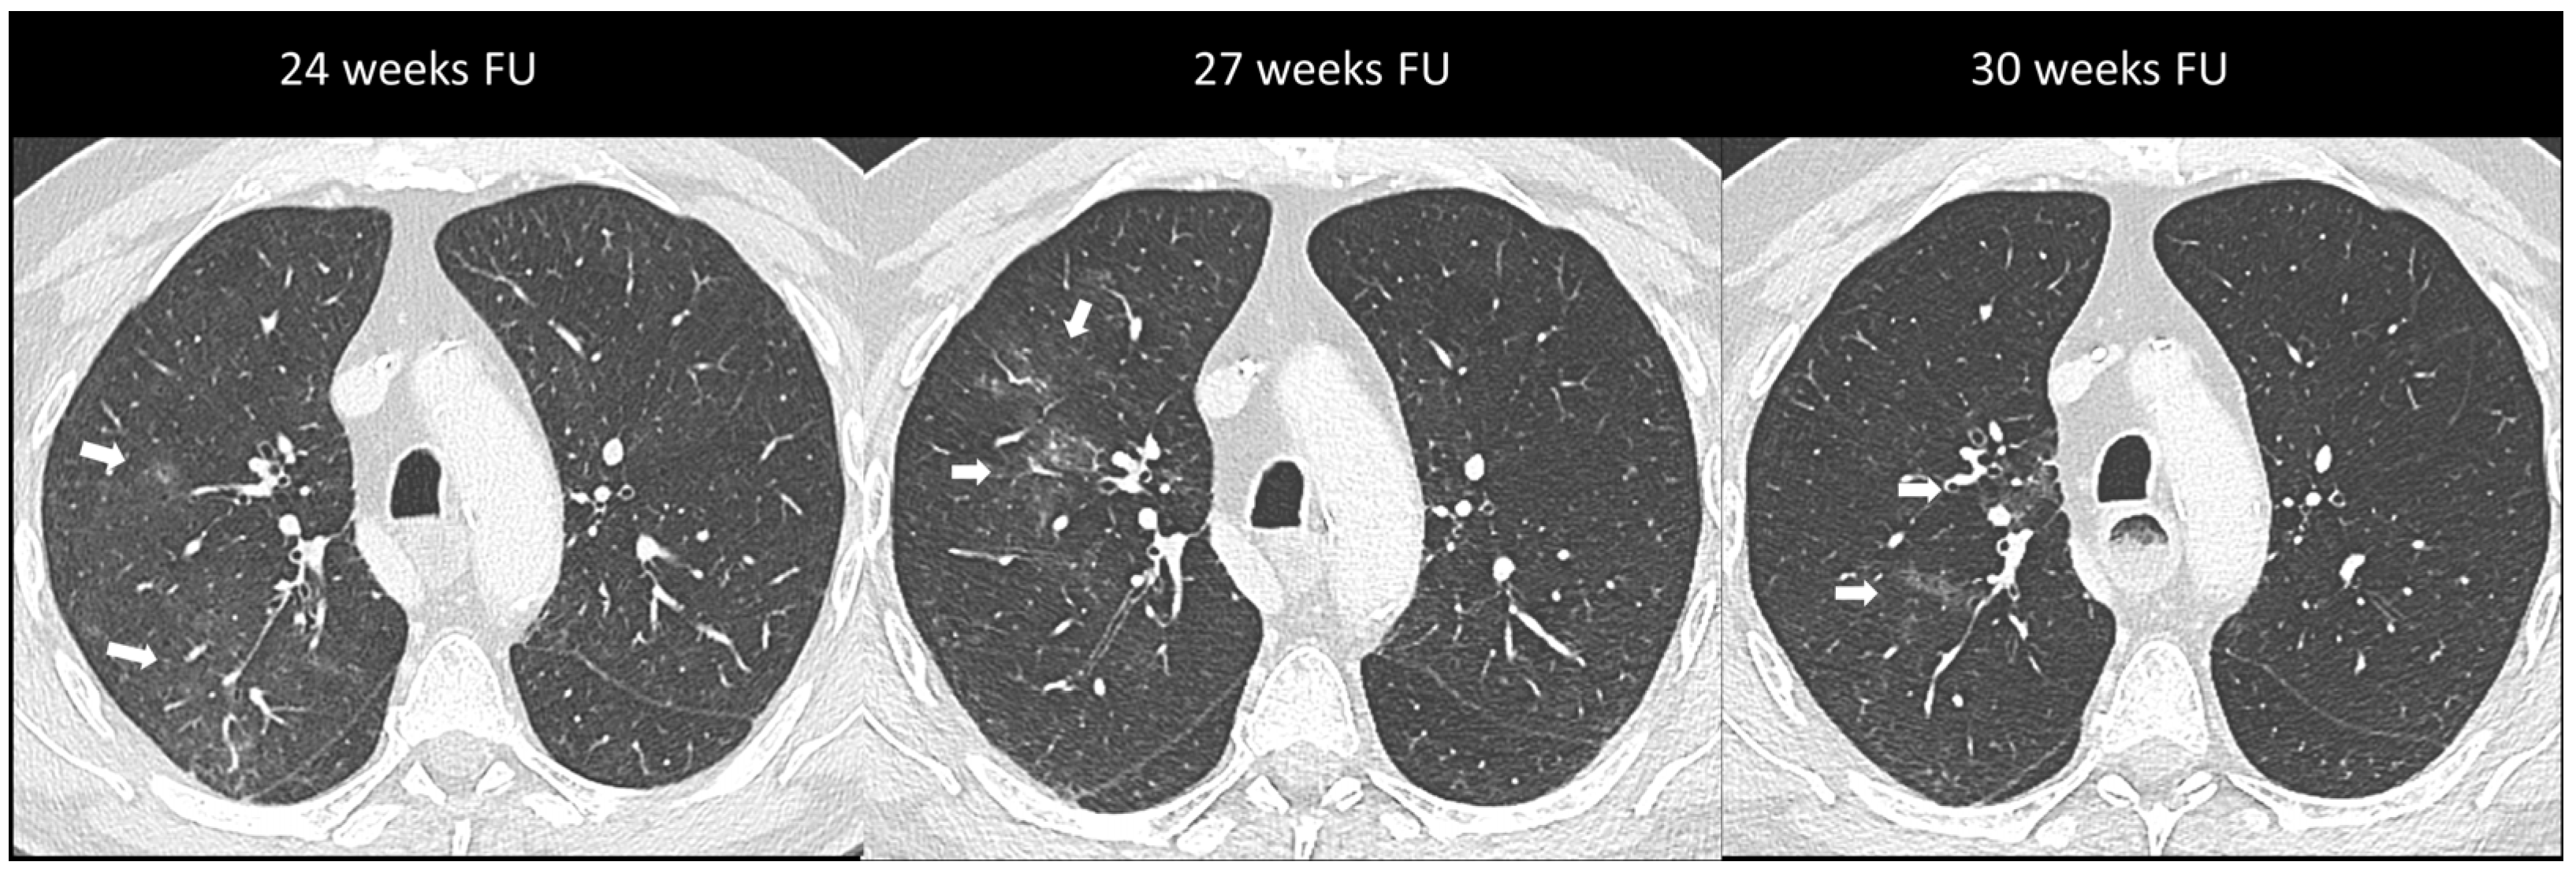

2.2.1. Ir-Pneumonitis

- Asher, N.; Marom, E.M.; Ben-Betzalel, G.; Baruch, E.N.; Steinberg-Silman, Y.; Schachter, J.; Shapira-Frommer, R.; Markel, G. Recurrent Pneumonitis in Patients with Melanoma Treated with Immune Checkpoint Inhibitors. Oncologist 2019, 24, 640–647. [Google Scholar] [CrossRef]

- Naidoo, J.; Cottrell, T.R.; Lipson, E.J.; Forde, P.M.; Illei, P.B.; Yarmus, L.B.; Voong, K.R.; Feller-Kopman, D.; Lee, H.; Riemer, J.; et al. Chronic immune checkpoint inhibitor pneumonitis. J. Immunother. Cancer 2020, 8, e000840. [Google Scholar] [CrossRef]

| Pneumonitis | OP | Multifocal, patchy, consolidations or GGOs with peribronchovascular and/or subpleural distribution | Migratory on a subsequent scan | Radiation Pneumonitis Infectious pneumonia Tumor progression |